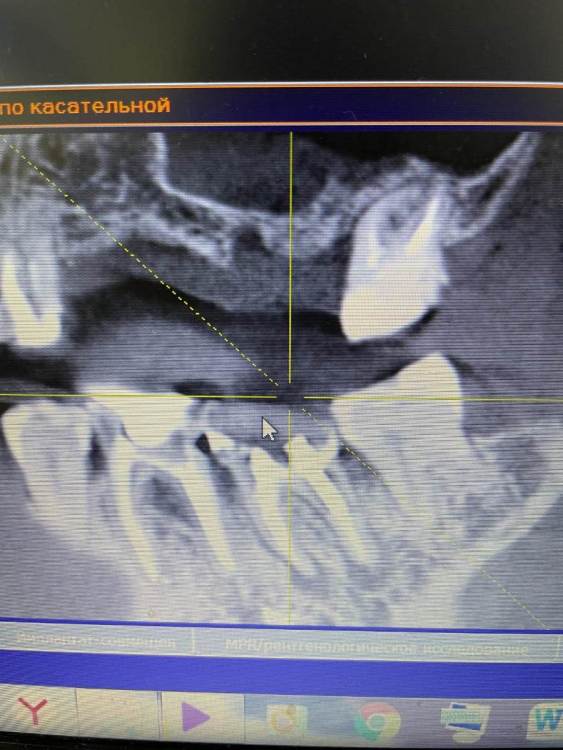

Irouil Опубликовано 21 октября, 2021 Поделиться Опубликовано 21 октября, 2021 Чтобы оценить прогноз перелеченных зубов надо увидеть ещё и снимки до лечения чтобы сравнить что было с тем, что стало. Такой вид снимка очень малоинформативен, я рекомендую либо выложить срезы из КТ интересующих Вас областей, либо выложить всю КТ 1 1 Ссылка на комментарий

Amparo743 Опубликовано 21 октября, 2021 Автор Поделиться Опубликовано 21 октября, 2021 @Irouil благодарю вас за ответ. К сожалению не знаю как извлечь из этой программы срезы или всю Кт. Мне отдали снимок на диске. И на этот снимок показывал врач и видел во всех этих зубах патологию, показывая именно с панорамы. Ссылка на комментарий

Irouil Опубликовано 21 октября, 2021 Поделиться Опубликовано 21 октября, 2021 Можете попробовать скинуть КТ в терапевтической ветке, тут надо его хорошенько посмотреть у каждого зуба чтобы оценить шансы на перелечивание, да и снимки до лечения было бы неплохо увидеть - может там динамика к улучшению стремится, но пока, судя по тем срезам что я вижу, вероятнее всего зубы действительно нужно будет удалять. Ссылка на комментарий

Bier Опубликовано 21 октября, 2021 Поделиться Опубликовано 21 октября, 2021 воспаление есть, скорее всего хирург прав, еще одно перелечивание они не перенесут. Ссылка на комментарий